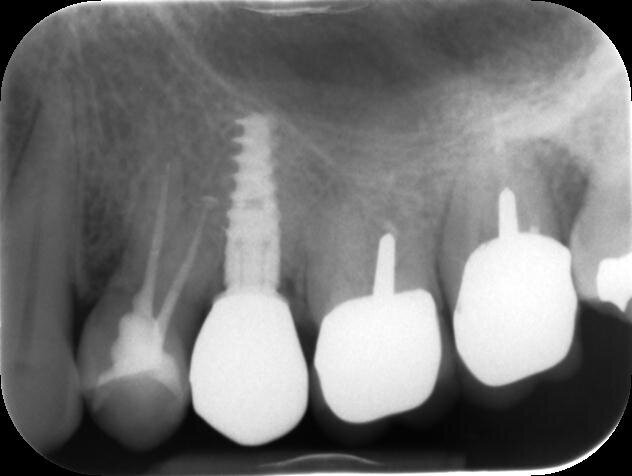

Si effettua prima una lastra endorale e in seguito una CBCT dell’elemento per valutare le possibilità di ritrattamento endodontico e la morfologia del difetto osseo, dalle quali si evince come le corticali appaiono essere mantenute ma che la porzione midollare dell’osso alveolare risulti completamente riassorbita. Gli elementi 26 e 27 presentano terapie endodontiche incongrue ma essendo asintomatici e privi di lesioni periapicali si sceglie insieme alla paziente di tenerli monitorati (Figg. 4, 5).